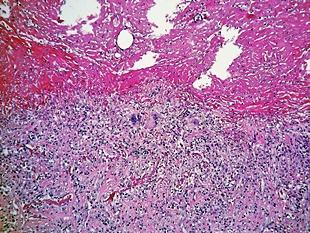

늑막에 생기는 염증으로 건성과 습성으로 나누어지는데요. 건성 늑막염의 경우 늑막에 섬유소가 침착되며, 습성 늑막염은 늑막강 속에 삼출액에 고이는 현상이 있어요. 화학요법으로 완치가 가능하며 심한 운동이나 과로가 원인이 되는 경우도 있다고 해요.

흉부X선 검사와 늑막 생검으로 진단이 가능해요. 청진시 호흡음이 감소되거나 가슴을 두드렸을 때 둔탁한 느낌이 들기도 합니다. 진단에 명확하지 않은 경우 흉강내시경을 이용하기도 해요.